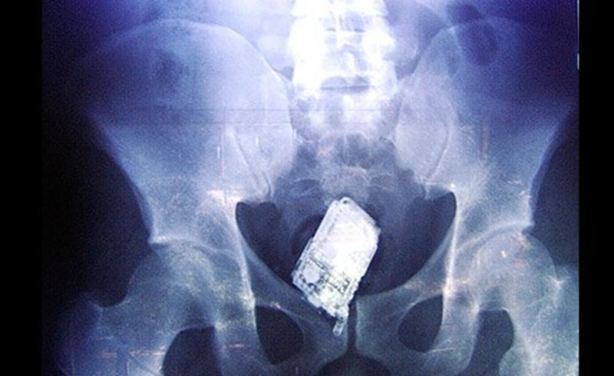

Bu karede ise Salvadoran Hapishanesi'nde yapılan aramada mahkumların vücutlarına gizledikleri cep telefonu gözüküyor.